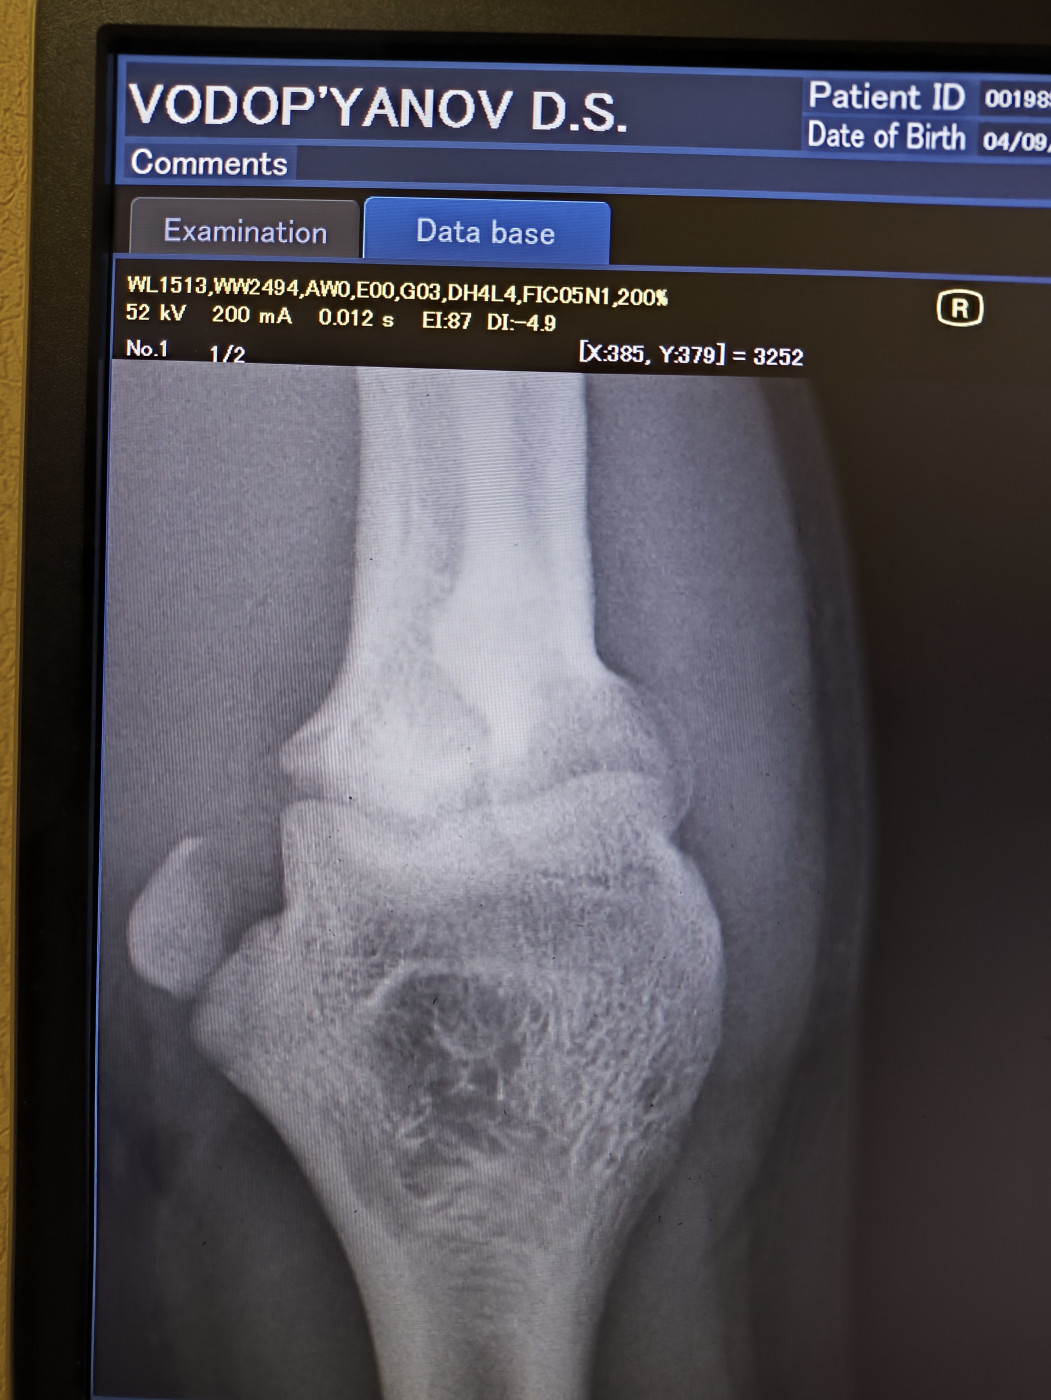

Боролся вчера на руках во время борьбы резкий хруст и не смог разгибать руку хотя при этом пальцы шевелятся, поехал в больницу и сказали что отломился кусочек кости, наложили гипс. Вопрос можно ли обойтись в данном случае только гипсом без операции,?